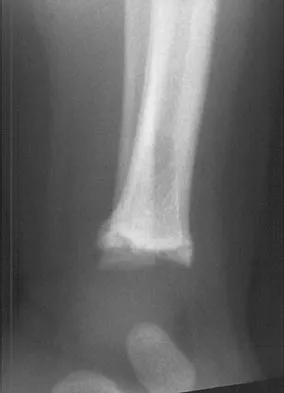

A 10-year-old boy with a history of retinoblastoma now reports right knee pain. AP and lateral radiographs are shown in Figures 3a and 3b. What is the most likely diagnosis?

Explanation

The radiographs show a bone-producing lesion in the femoral diaphysis. The radiographic appearance of small round cell tumors is more permeative with an elevated periosteum and no matrix production. The appearance of this lesion is most consistent with osteosarcoma. Patients who carry the Rb gene are predisposed to osteosarcoma. However, Ewing's sarcoma, primitive neuroectodermal tumor, and osteomyelitis can all occur in this location. Unni KK: Dahlin's Bone Tumors: General Aspects and Data on 11,087 Cases, ed 5. Philadelphia, PA, Lippincott-Raven, 1996, pp 143-160.